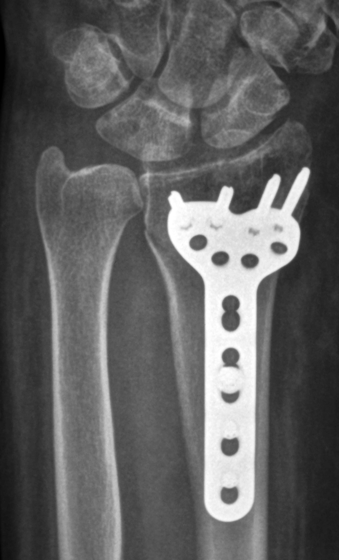

Open reduction and internal fixation

Some fractures can not be reduced by manipulation and these require surgery to reduce the bone fragments from inside. This is more likely to be required with fractures involving the joint surface or those in the younger patients. A cut is made in the skin and once the fracture has been reduced, a metal plate and screws are used to hold the fracture. Because the fracture is held securely the wrist can be mobilised as soon a the discomfort subsides, usually within 2 weeks of the surgery.